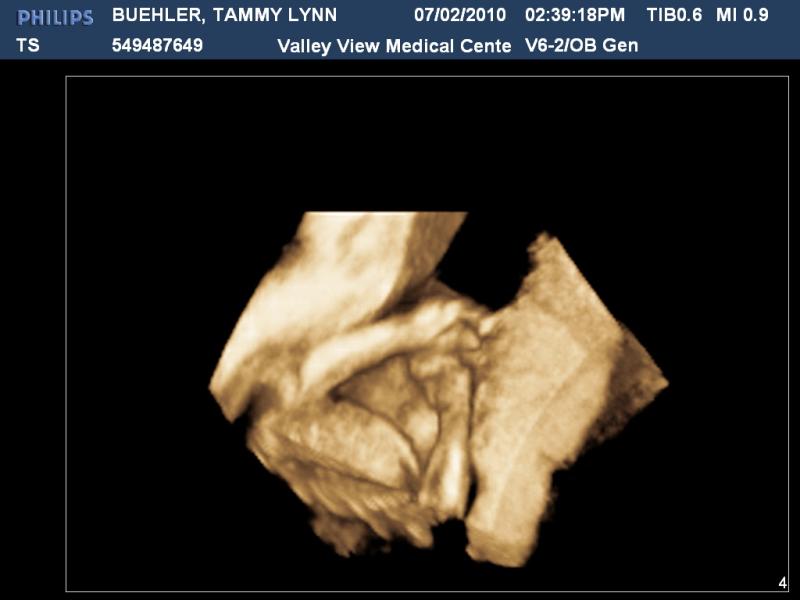

3D picture of Arms